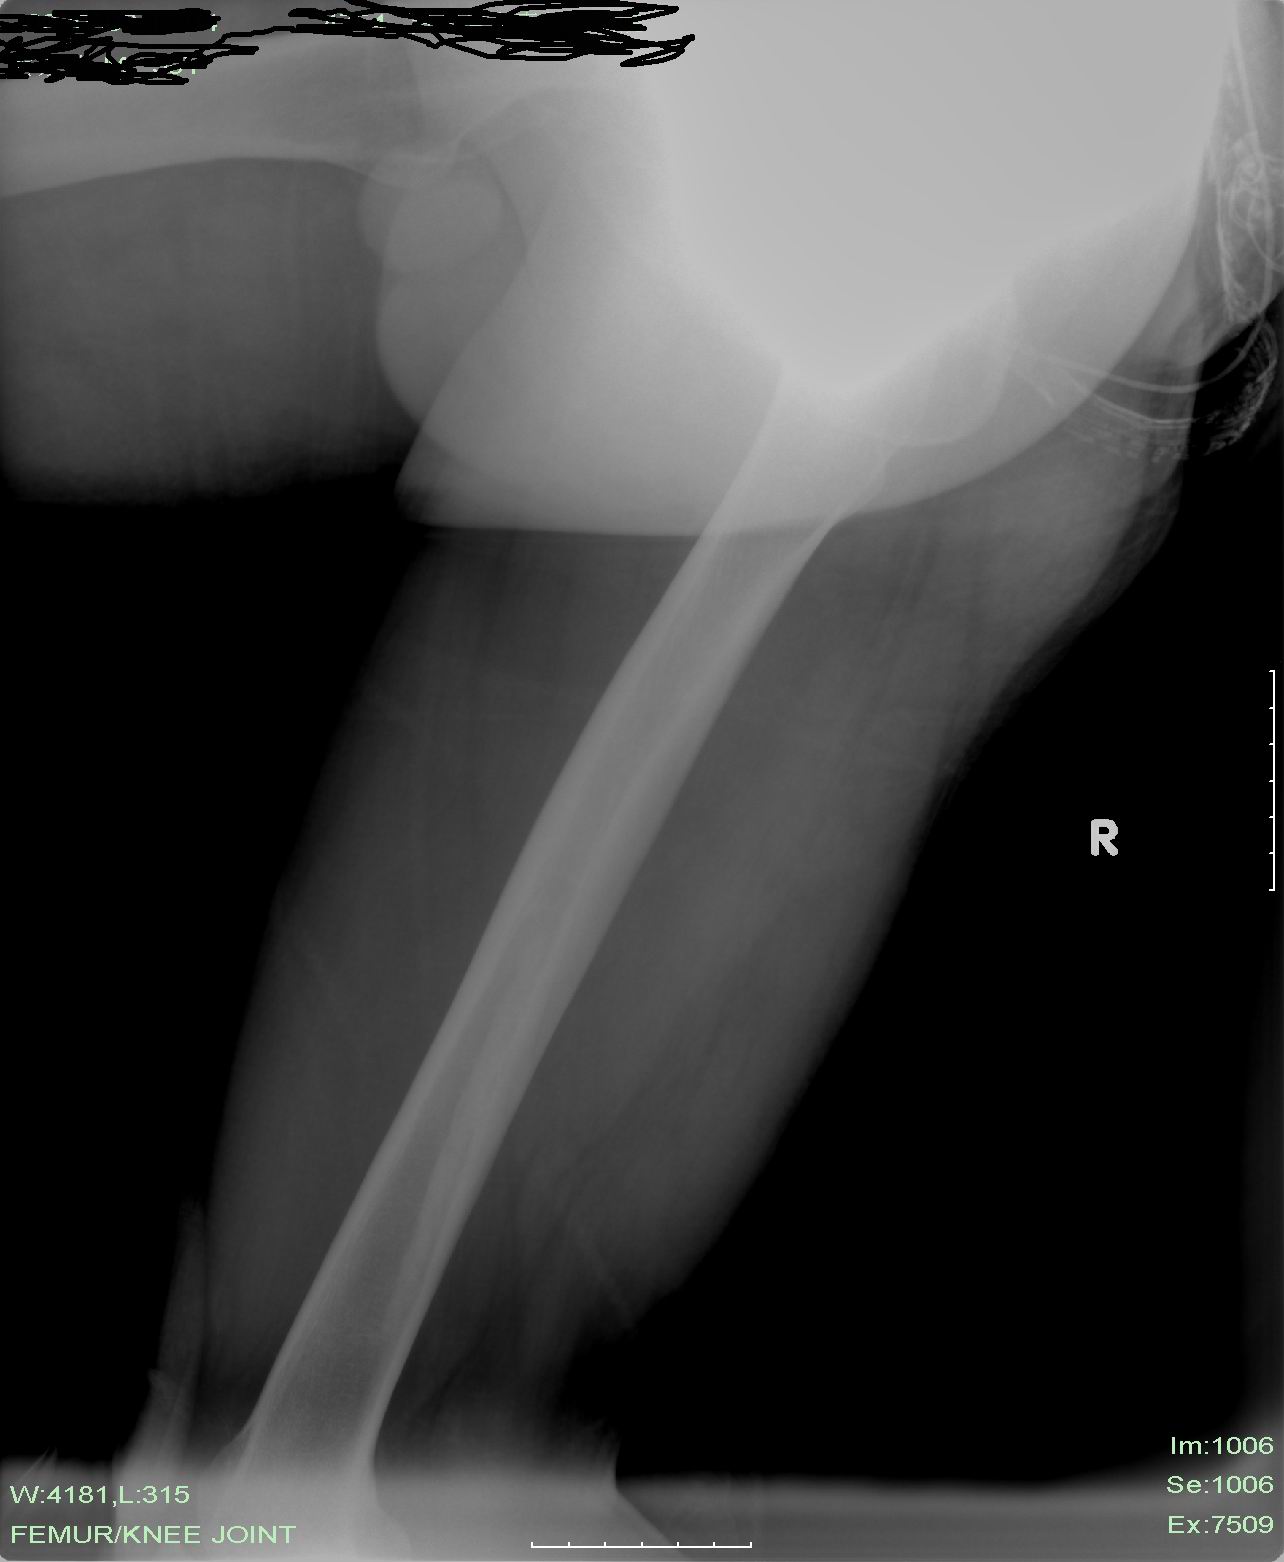

标题: X5404:右大腿突发疼痛3天,查无特殊。我看没什么问题,临 [打印本页]

标题: X5404:右大腿突发疼痛3天,查无特殊。我看没什么问题,临

临床的说有问题是对的,因为患者右大腿疼痛。我们平片所及的没见有问题,此问题该临床开动脑筋继续找。

应该是平片未见异常;临床说有问题是因为病人有疼痛,可进一步检查。

x片未见明显异常,做进一步检查和考虑软组织病变~